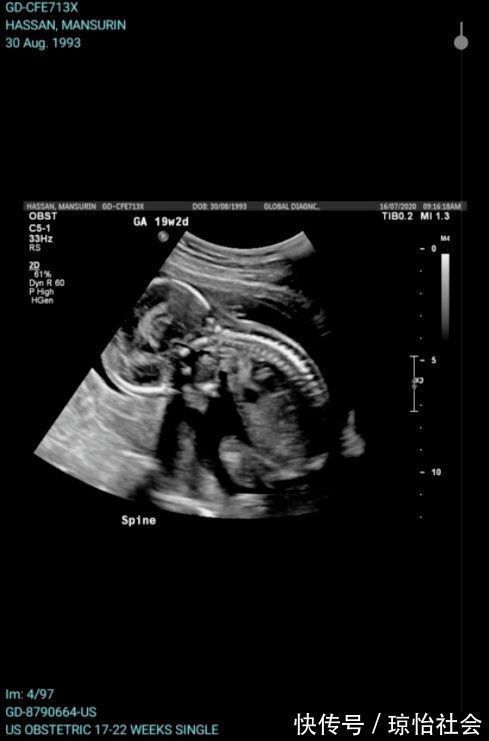

事件的主人公Sarah Hassan和丈夫Sunny Alam在两年前移民到了澳洲,

在移民澳洲不久后,Sarah就怀孕了。

2020年12月9日,Sarah在预产期的第二天开始宫缩,

在丈夫的陪同下,Sarah住进了St John of God Bunbury Hospital进行检查。